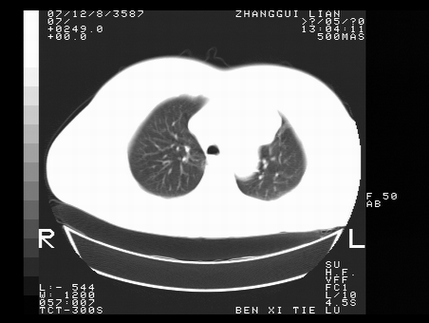

标题: CT10817:女,46,胸疼,无其他病史 [打印本页]

标题: CT10817:女,46,胸疼,无其他病史

左侧上纵隔旁团块影,部分植入纵隔,与纵隔界限不清,另:左肺门明显见团块,气管隆突前方见肿大淋巴结。考虑:左上肺纵隔型肺癌伴左肺门及纵隔淋巴结转移!

1左上肺中心型肺癌伴左肺上叶不张2主动脉弓旁淋巴结转移3左下肺炎症

1 左侧中央型肺癌伴阻塞性肺炎 2 左肺门及纵隔淋巴结转移!3两侧胸腔及心包积液.

左侧胸廓塌陷,纵隔向左侧移位,左上肺不张。

1 左侧中央型肺癌伴阻塞性肺炎

2 左肺门及纵隔淋巴结转移!

3两侧胸腔及心包积液.